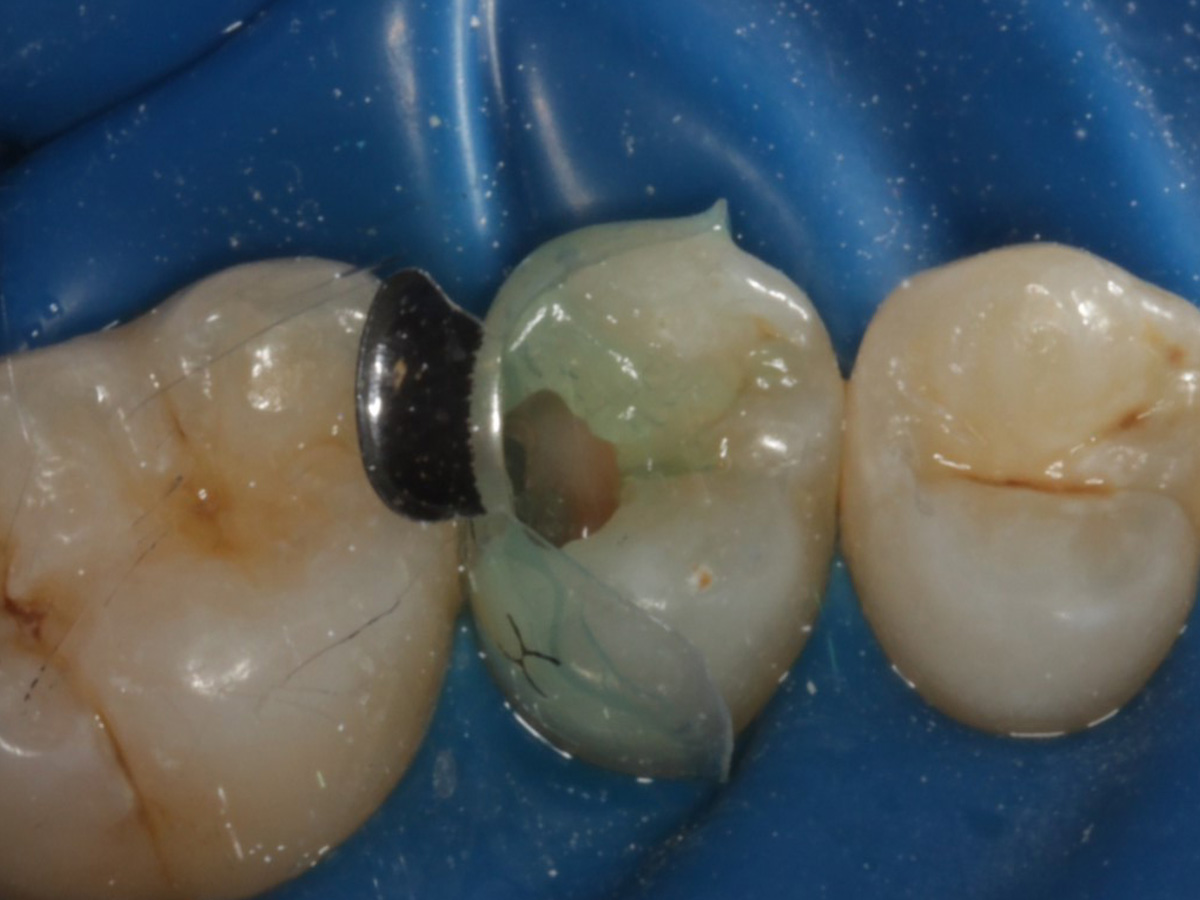

Abbildung 10

Nach Applikation der Matrize: Evolve Schwarz Prämolar- 7 mm; Schmelzätzung